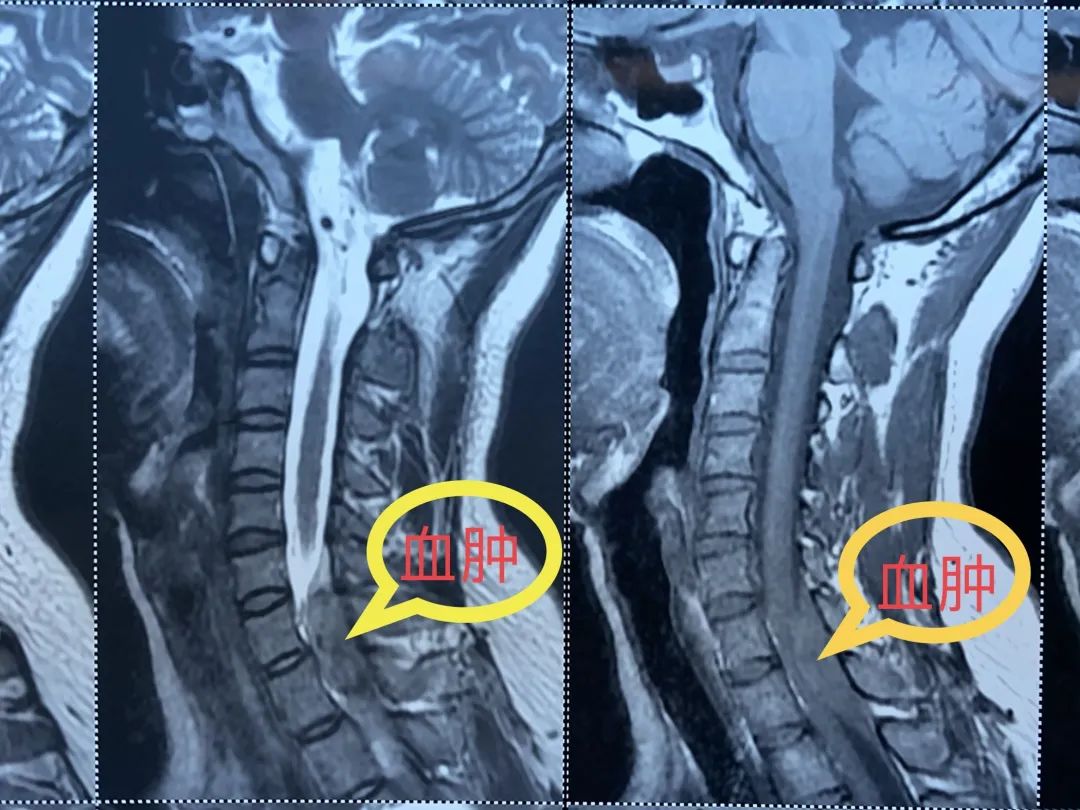

医生为患者申请紧急核磁检查,结果显示:颈髓有一个巨大的肿物压迫着。

随后,小真被转到了神经外科治疗,经神经外科医生判断,小真的情况是颈椎管内急性出血导致的,而不正确的扭动脖子和推拿按摩很可能是主要原因。

必须尽快手术解除脊髓压迫,若坚持保守治疗可能病情恶化,出现永久高位截瘫。